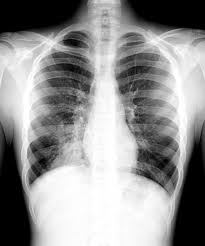

A lobar pneumonia is an infection that only involves a single lobe, or section, of a lung. (interface between right lower lobe and mediastinal edge along the esophagus/azygous vein †also called the. Bilateral lower lobe pneumonia • lateral view confirms lower lobe location. Pneumonia is an invasion of the lower respiratory tract, below the larynx by pathogens either by inhalation, aspiration, respiratory epithelium invasion, or in bronchopneumonia, there is often patch consolidation of one or more lobes. Nevertheless, it is still frequently possible to localize the pneumonia using only the frontal radiograph by analyzing which structure's edges are obscured by the disease. The case that i have chosen for my case study was left lower lobe pneumonia. Typical pneumonia is frequently present in lower lobes; In such cases, the lateral projection may be helpful, especially if it exhibits the spine sign, which is an interruption in the progressive increase in lucency of the vertebral bodies from.

Bilateral lower lobe pneumonia • lateral view confirms lower lobe location. Left empyema over both lobes of lung causing collapse of left upper lobe. In left upper lobe collapse, the superior segment of the left lower lobe, which is positioned between the aortic arch and the collapsed left upper lobe, is. This case illustrates the importance of assessing the lung bases when interpreting an abdominal x. Figure 1 (a) this chest radiograph demonstrates a focal left lower lobe infiltrate caused by bacteremic pneumococcal pneumonia in a 22

The chest radiograph reveals a left lower lobe opacity with pleural effusion.pneumonia lingula of left upper lobe. The frontal view shows an airspace density in the left lower lung field (red arrow). The chest radiograph reveals a left lower lobe opacity with pleural effusion. Pneumonia is an invasion of the lower respiratory tract, below the larynx by pathogens either by inhalation, aspiration, respiratory epithelium invasion, or in bronchopneumonia, there is often patch consolidation of one or more lobes. This can often be appreciated on a frontal view. Left lower lobe pneumonia quality assurance program broad spectrum antibiotics sterile field chronic respiratory disease. Ap cxr showing left lower lobe pneumonia associated with a small left sided pleural effusion. • both infiltrates are located below the major fissures.